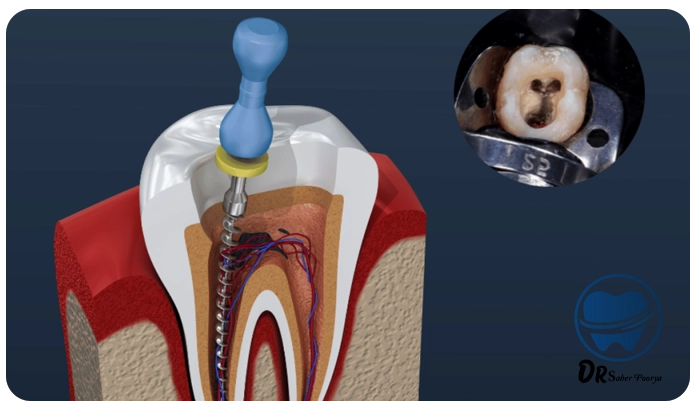

مراحل درمان ریشه (عصبکشی) معمولاً در چند گام دقیق و برنامهریزیشده انجام میگیرد.

هدف این فرآیند، حذف عفونت از داخل دندان و حفظ آن برای ادامه عملکرد طبیعی در دهان است.

بیحسی و دسترسی به پالپ دندان

پس از معاینه، بیحسی موضعی برای ناحیه مربوطه تزریق میشود تا بیمار هیچگونه دردی احساس نکند.

سپس دندانپزشک با ایجاد حفرهای کوچک در تاج دندان، به ناحیه داخلی (پالپ) دسترسی پیدا میکند و قسمتهای پوسیده را حذف مینماید.

خارج کردن بافت عفونی

در این مرحله، بافت آسیبدیده و عفونی درون کانالهای ریشه بهطور کامل تخلیه میشود.

هدف، حذف کامل اعصاب و عروق داخل دندان است تا از بروز درد یا عفونت مجدد جلوگیری شود.

شستشو و پاکسازی کانالها

کانالهای دندان پس از تخلیه، باید با دقت ضدعفونی و پاکسازی شوند. برای این کار، محلولهای مخصوصی استفاده میشود

که هم باقیماندههای عفونی را از بین میبرند و هم به از بین رفتن باکتریها کمک میکنند.

پر کردن کانالها

بعد از پاکسازی کامل، دندانپزشک از مادهای خاص بهنام گوتاپرکا برای پر کردن کانالهای ریشه استفاده میکند.

سپس برای محافظت موقت از دندان، پانسمان موقتی روی آن قرار داده میشود.